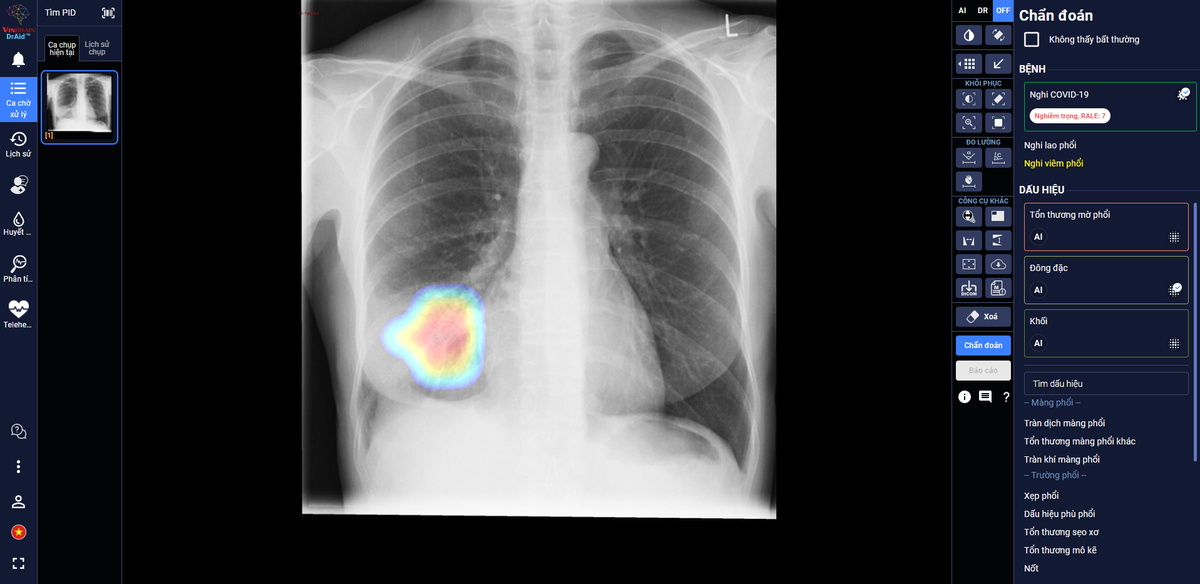

DrAid giúp bác sĩ theo dõi mức độ tổn thương phổi ở một bệnh nhân F0 trên ảnh X-quang phổi.

Trong các bệnh viện thu dung điều trị COVID-19, DrAid cho COVID-19 giúp các bác sĩ đánh giá mức độ tổn thương phổi của bệnh nhân COVID-19 qua các ngày, từ đó đưa ra các chỉ định điều trị kịp thời và hiệu quả cho bệnh nhân.

Theo đánh giá của các bác sĩ tại Trung tâm Y tế Kỳ Anh – Hà Tĩnh, AI đã giúp đỡ các bác sĩ khá nhiều khi theo dõi tổn thương qua các ngày, nhận diện rõ ràng là tổn thương lan rộng như thế nào. Ngoài ra, AI cũng giúp bác sĩ nhận diện các tổn thương nhỏ dễ bỏ sót.